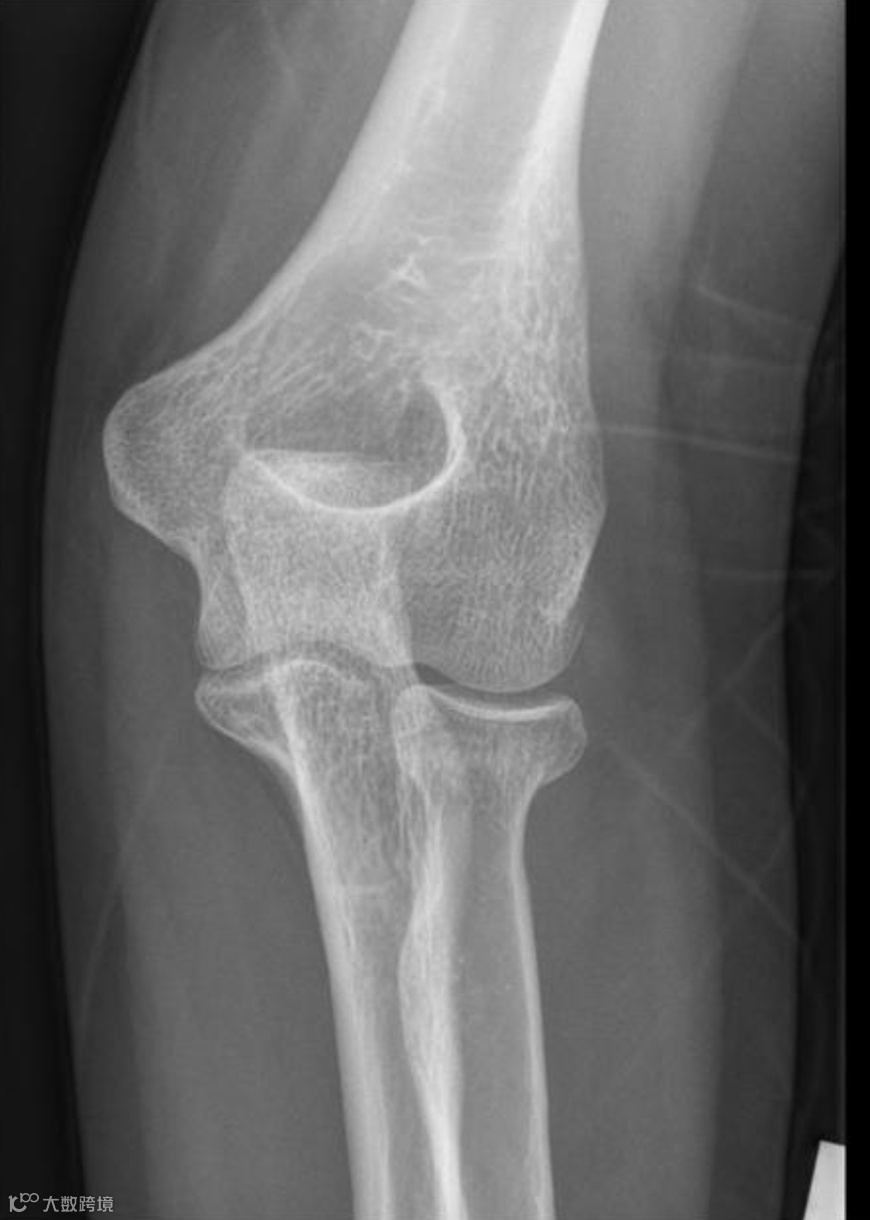

在正常的肘关节侧位X光片上:

前脂肪垫:有时可以隐约看到,表现为紧贴骨骼的一条细线状或窄三角形低密度阴影。

后方脂肪垫:因为深埋在鹰嘴窝里,正常情况下在X光片上是看不见的。

正常肘关节X线侧位,前脂肪垫(红色箭头)为紧贴肱骨的一条细线状或窄三角形低密度影,后脂肪垫(黄色箭头)看不见。